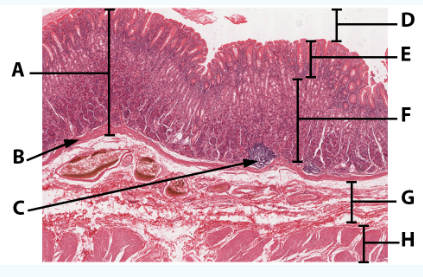

A

Mucosa: simple columnar epithelium with microvilli

B

Submucosa

C

muscularis mucosa

Area

Small intestine

E

simple columnar epithelium with goblet cells and microvilli

F

Villi

G

Lamina propria